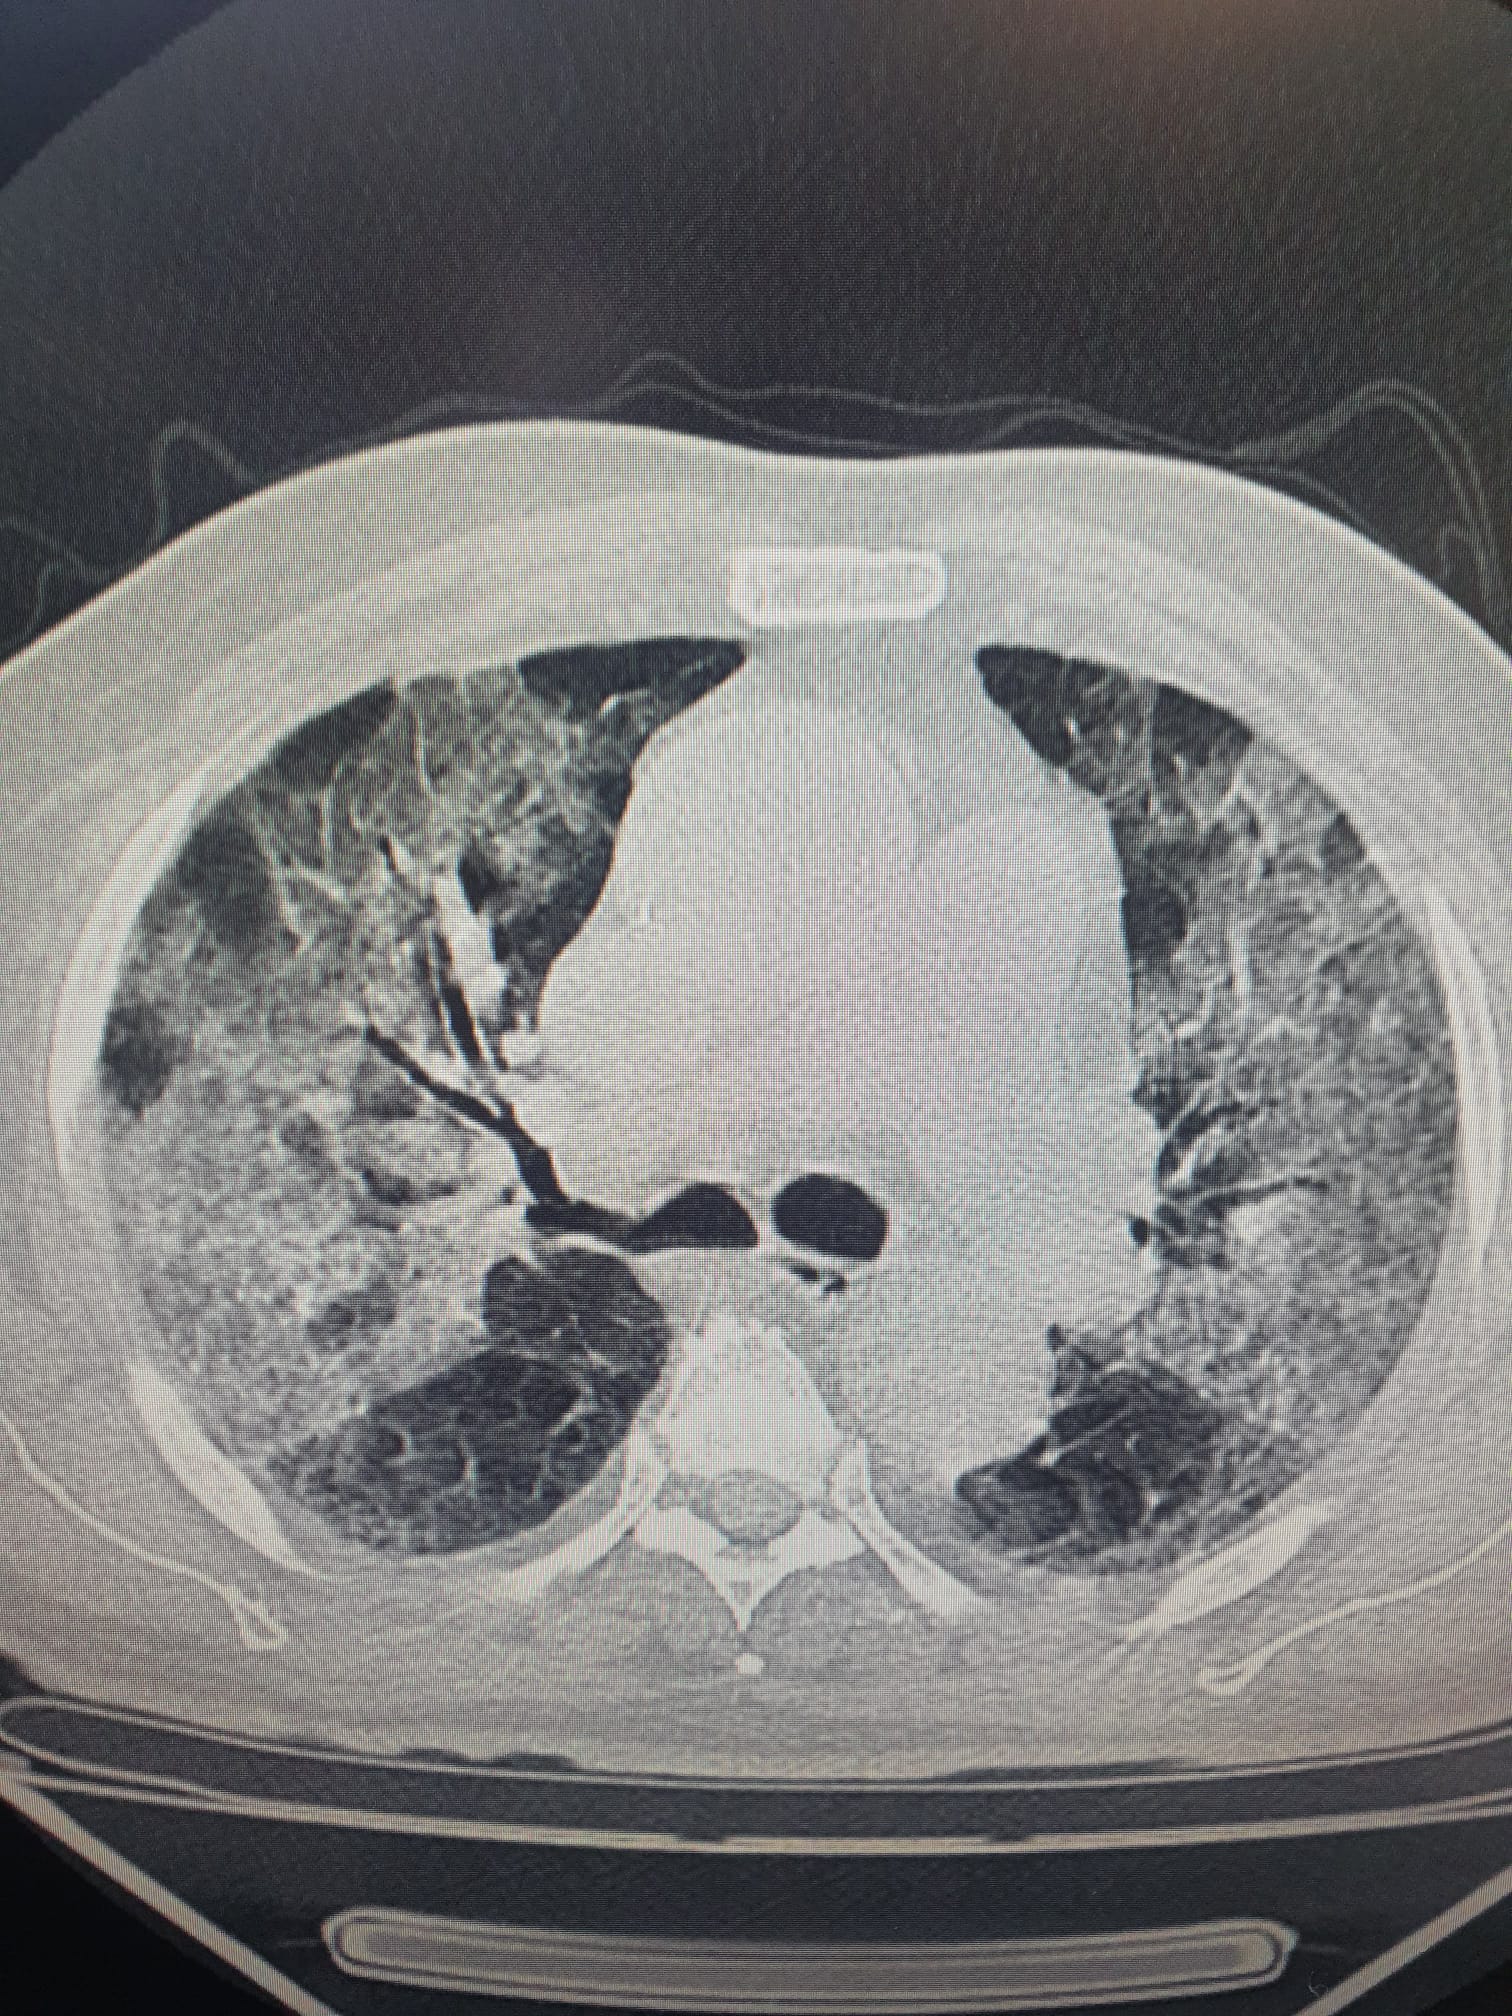

Özkaya, Samsun'da ciddi bir artışın olduğunu belirterek, "Tüm dünyada Maymun Çiçeği virüsu alarmı verilirken, Covid-19 virüsünün halen aramızda olduğu unutuluyor. Son haftalarda Covid vakalarının arttığını söylemiştik. Ancak akciğer tutulumları hafif olarak devam etmekle birlikte, son günlerde ciddi akciğer tutulumlarında ve hastane yatışlarında da artış var. Özellikle yaşlı hastalarda yoğun bakım yatışları ve nadir ölümler de görülmeye başladı. Maymun Çiçeği virüsü bulaşma yöntemi çok farklı olup, ülkemiz için salgın tehditi oluşturmuyor. Ancak Covid-19 virüsü halen aramızda ve sinsi ölümcül bir tehdit oluşturmaya devam ediyor" dedi.